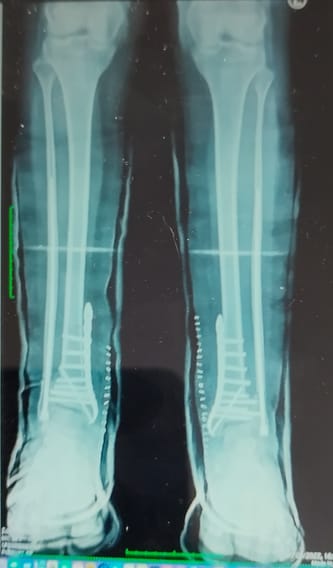

Przed Mateuszem ostatni etap leczenia operacyjnego .Nie zatrzymujmy się na finiszu .Wpłata zaliczki do końca listopada zapewni Mu konkretny termin operacji .